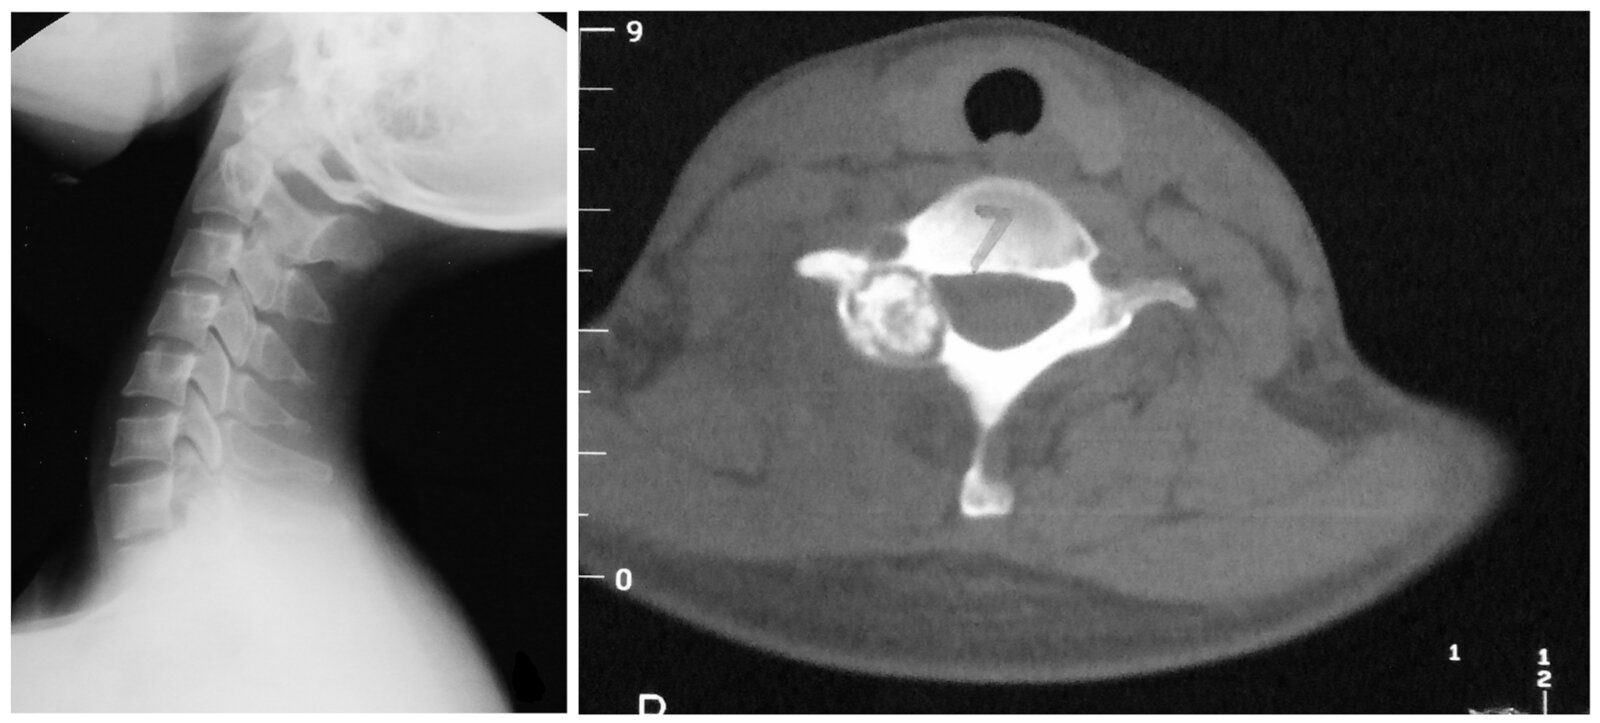

Osteoid osteoma [4]

• Description

• Small tumor (< 2 cm)

• Predominantly located in the cortex of long bones

• Epidemiology

• Peak incidence: 4–25 years [5]

• Sex: ♂ > ♀

• Clinical features

• Located in metaphysis and diaphysis of long bones (predominantly the proximalfemur, tibia, and humerus) and vertebrae

• Constant, intense pain that worsens at night

• Pain is responsive to NSAIDs (e.g., ibuprofen, aspirin)

• Diagnostics

• X-ray or CT: radiolucent core (osteoid), surrounded by perifocal sclerosis (nidus)

• Scintigraphy: usually intense enhancement

• Double-density sign

• Intraoperative nuclear imaging using a probe to detect the tumor

• Treatment: NSAIDs or surgical removal if pain is unresponsive to medical treatment